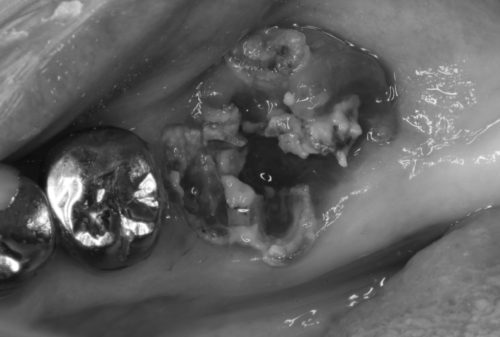

何とか残そう、使えるだけ使おう、としても難しい歯もあります

そんな歯は残念ながら、本人と相談し、抜歯を選択して頂きます

勿論写真を撮影して、見て頂きます